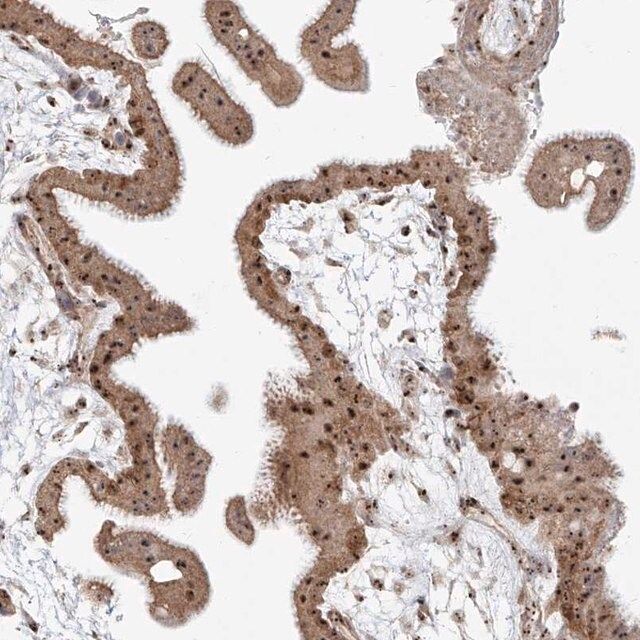

BYSL antibody Immunohistochemistry, Western, Immunofluorescence HPA031219

Anti-BYSL antibody (ab251811) | Abcam

BYSL antibody (28319-1-AP) | Proteintech